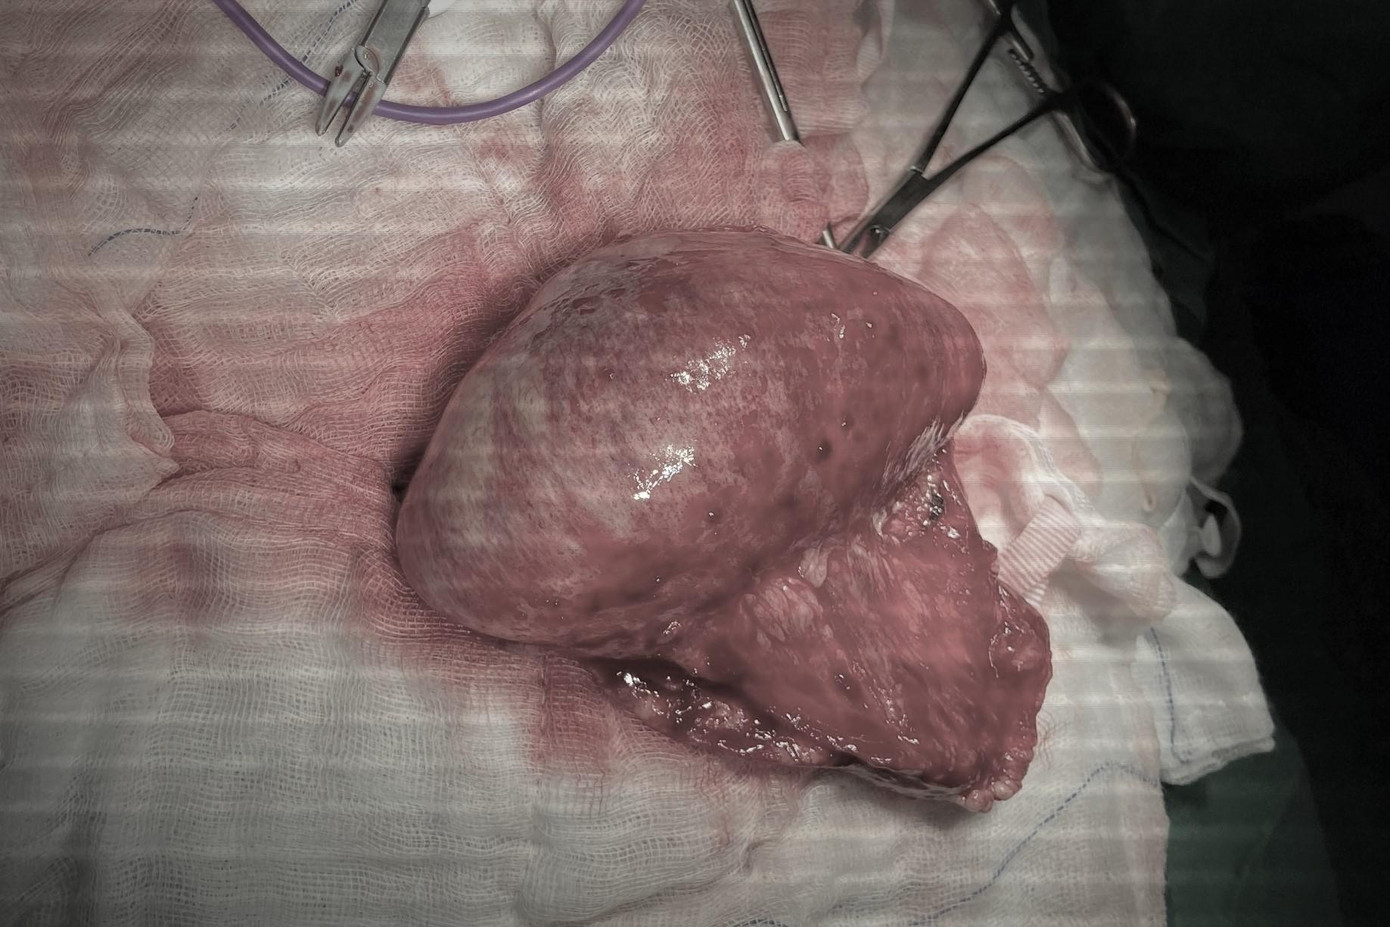

Ngay lập tức, trẻ được chỉ định mổ cấp cứu. ThS.BS Nguyễn Trần Việt Tánh, khoa ngoại tổng hợp cho biết, trong quá trình phẫu thuật ê kíp bác sĩ ghi nhận phần lớn ruột già của bệnh nhi dãn lớn, ứ nhiều phân, bị viêm hư hại gần như toàn bộ. Nghiêm trọng hơn, vị trí đại tràng ngang (phần ruột già nằm giữa bụng) bị thủng khiến phân thoát vào ổ bụng gây nhiễm trùng nhiễm độc, đe dọa tính mạng bệnh nhi.

![]() |

| Các bác sĩ buộc phải cắt đại tràng của bệnh nhi, loại bỏ triệt để ổ nhiễm trùng |

Ê kíp phẫu thuật đã nhanh chóng cắt bỏ hoàn toàn ổ nhiễm trùng tại đại tràng viêm hoại tử, làm sạch ổ bụng. Sau 1 tuần điều trị, hậu phẫu tích cực tại khoa hồi sức, chiều 16/3 sức khoẻ bệnh nhi đã cải thiện tốt, ăn uống được và chuẩn bị xuất viện.